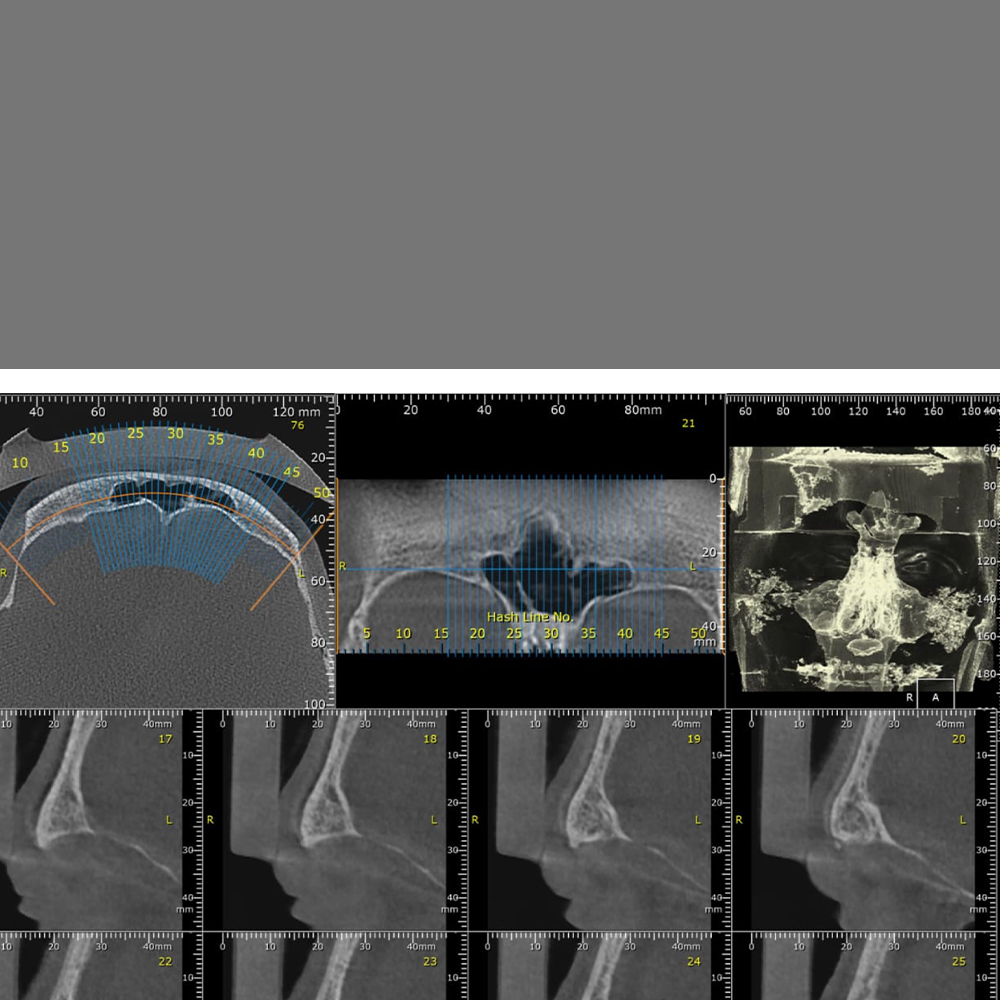

3D ATM

Tomografia computerizată (CBCT) a articulației temporo-mandibulare (ATM) permite o analiză 3D detaliată a componentelor osoase ale acestei articulații.

300 RON